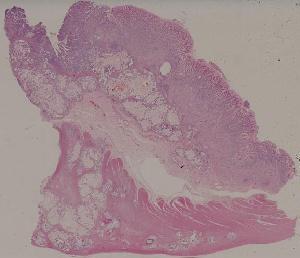

66.活动性结节性肝硬化

低倍视野